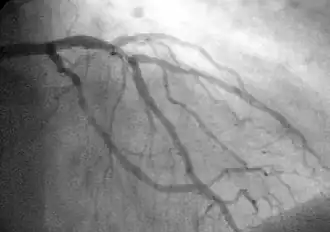

A coronary angiogram (an X-ray with radiocontrast agent in the coronary arteries) that shows the left coronary circulation. The distal left main coronary artery (LMCA) is in the left upper quadrant of the image. Its main branches (also visible) are the left circumflex artery (LCX), which courses top-to-bottom initially and then toward the centre/bottom, and the left anterior descending (LAD) artery, which courses from left-to-right on the image and then down the middle of the image to project underneath the distal LCX. The LAD, as is usual, has two large diagonal branches, which arise at the centre-top of the image and course toward the centre/right of the image.